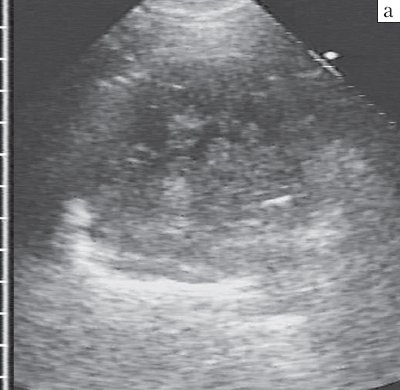

Блокированный абсцесс представлял собой раннюю, закрытую, стадию деструкции легкого с образованием гнойной полости, окруженной легочной паренхимой и не сообщавшейся с бронхиальным деревом. Эхографически он имел вид округлого очага, чаще с однородной эхоструктурой, представленной ан- или гипоэхогенным жидким содержимым с эхогенной взвесью (гнойный детрит), но без гиперэхогенных сигналов от воздуха. Взвесь различалась по эхогенности, плотности и характеру распределения в полости деструкции. Как правило, она была мелкозернистой, достаточно рыхлой и диффузно заполняла весь абсцесс, не вызывая диагностических трудностей (рис. 2).

а) Анэхогенным содержимым с мелкозернистой редкой взвесью.